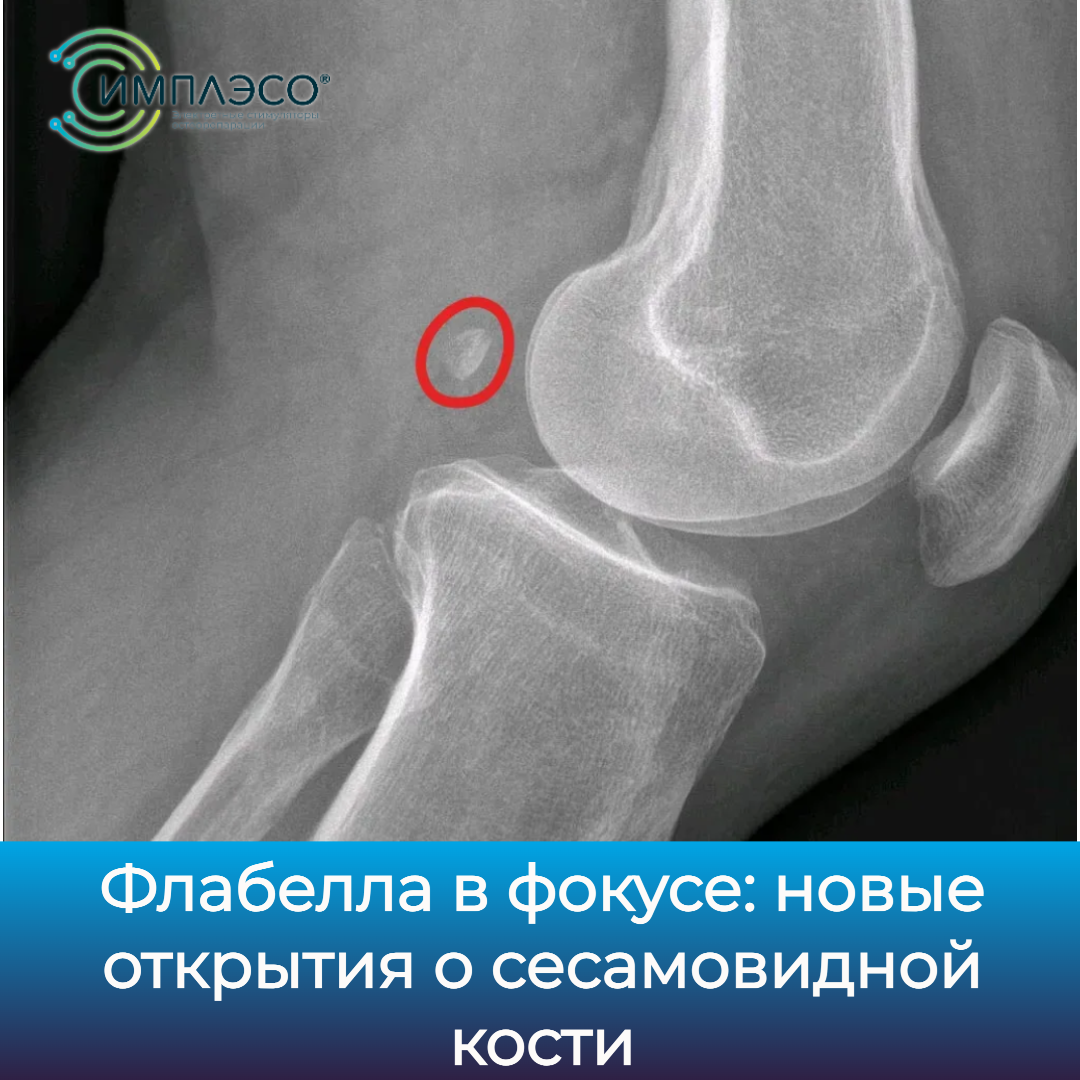

Флабелла в фокусе: новые открытия о сесамовидной кости

Флабелла располагается в толще сухожилия четырехглавой мышцы бедра (квадрицепса) прямо под коленной чашечкой. Ее основная функция - защищать сухожилие от истирания о кость при сгибании и разгибании колена. Также флабелла увеличивает рычаг действия квадрицепса, усиливая его тягу.

Рост флабеллы обусловлен генетически, но вот ее окостенение у всех происходит в разном возрасте и, возможно, зависит от механических причин. Чаще ее встречают у людей после 70 лет, но она может появиться уже у 12-летних.